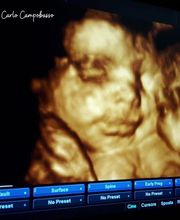

OstetriciaGalleria